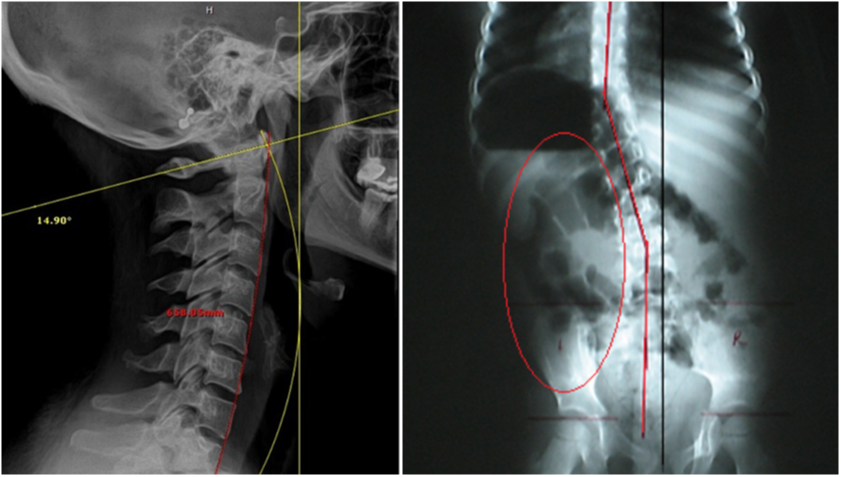

- Our system is a biomechanical analysis of spine kinematics (or spinal motion), utilizing “stress views” of the spine (flexion, extension, rotation...

- And/or lateral bending views where required) or videofluoroscopy (VF, or “moving x-ray” studies) to determine the loss of spinal function, which is at the core of the “vertebral subluxation complex”.

2. DIGITAL SPINAL RADIOGRAPHY

PRS also utilizes static X-ray, to provide precise, spinal alignment studies and rule out pathologies.

By providing a clear baseline for further diagnosis and care, static X-rays enable chiropractors to develop targeted strategies tailored to each patient’s needs.

Serving as the cornerstone for our more advanced technologies and techniques, this method ensures a solid starting point, empowering practitioners to build upon accurate data for optimal spinal correction and lasting patient outcomes.